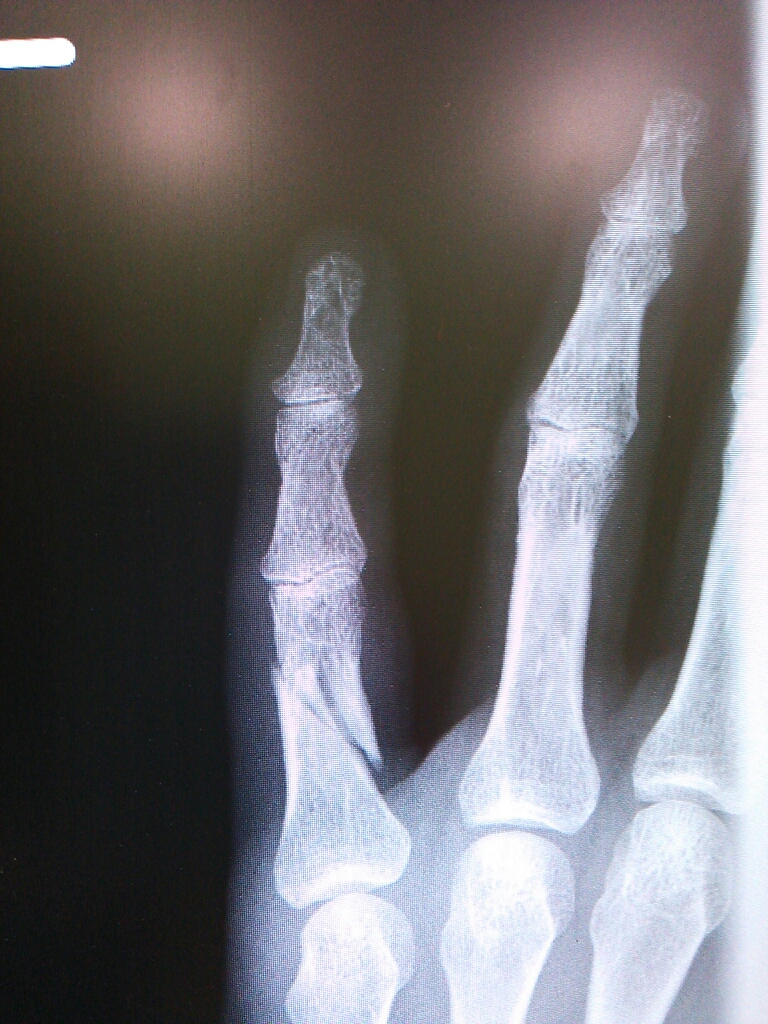

金曜にレントゲン撮ったけどあんまり変わってない…。

何故だか添え木は外され指を動かすリハビリモードに切り替わった!?

まだくっついてないし痛いんですけど…。